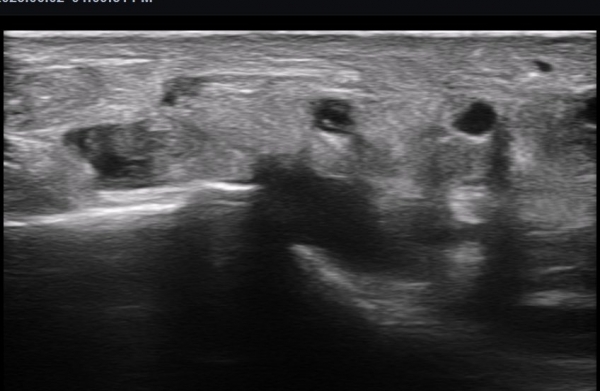

ÃÊÀ½ÆÄ ¼Ò°ß : ºñº¹½Å°æ Ⱦ´Ü¸é°Ë»ç¿¡¼­(»çÁø 1~13) ºñº¹½Å°æÀÇ Àú¿¡ÄÚ ºÎÁ¾°ú ´Üºñ°ñ°Ç³» ³¶Á¾¼º º´º¯ÀÌ °üÂûµÈ´Ù.

ºñº¹½Å°æ Á¾´Ü¸é°Ë»ç(»çÁø 14, 15)¿¡¼­ ºñº¹½Å°æÀÇ Àü¹ÝÀûÀÎ Àú¿¡ÄÚ ºÎÁ¾°ú ºñº¹½Å°æ ½ÉÃþÀ¸·Î ´Üºñ°ñ°Ç³»

³¶Á¾¼º º¯º¯ÀÌ °üÂûµÈ´Ù.